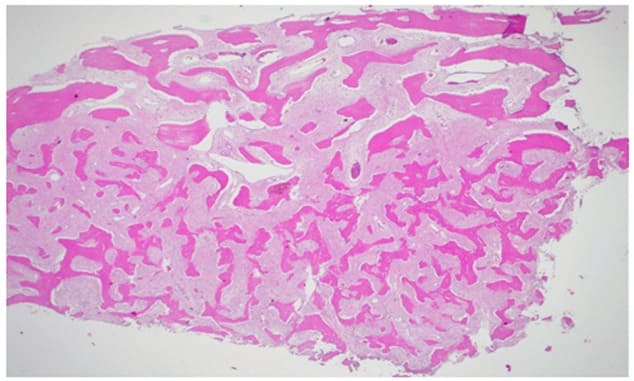

Histopathological Features:

Figure 11: H&E 100X, highlights of the fibrous component.